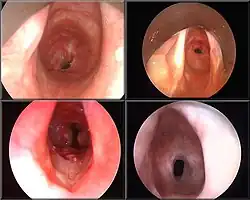

Обтурация

Обтура́ция (лат. obturatio «закупоривание») — закупорка полого анатомического образования (кровеносного сосуда, жёлчного протока, мочеточника, бронха, кишечника и т. д.) с нарушением его проходимости[1]. Нарушение проходимости может развиваться как в связи с патологией в пределах полого органа, так и из-за его сдавления извне (например, опухолью). В качестве синонимов обтурации используются термины обструкция и окклюзия: